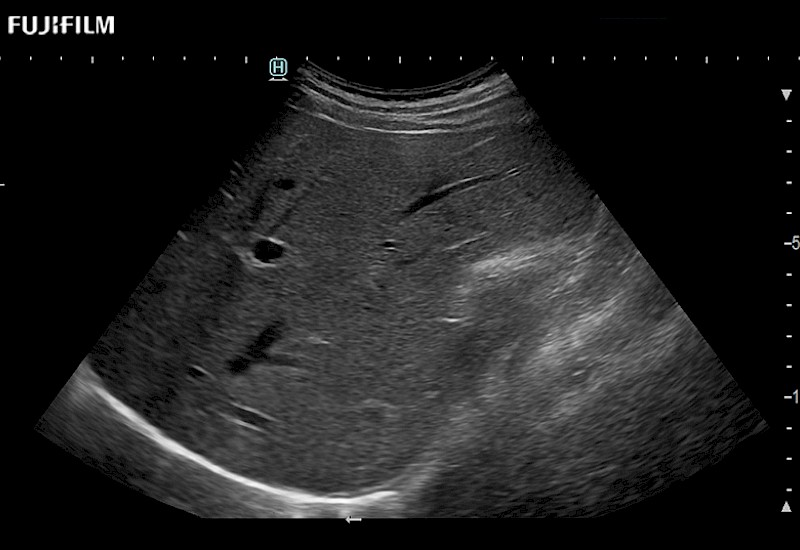

Extraordinary high-resolution digital imaging

- Exceptional near and far-field resolution

- Instant feedback on tumor margin delineation

- Valuable information to guide tumor resections

- Ideal for liver and kidney scanning

- Exceptional near and far-field resolution

- Instant feedback on tumor margin delineation

- Ideal for liver and kidney scanning

- Exceptional near and far-field resolution

- Instant feedback on tumor margin delineation

- Ideal for liver and kidney scanning

- Exceptional near and far-field resolution

- Instant feedback on tumor margin delineation

- Ideal for liver and kidney scanning

- Exceptional near and far field resolution

- Instant feedback on tumor margin delineation